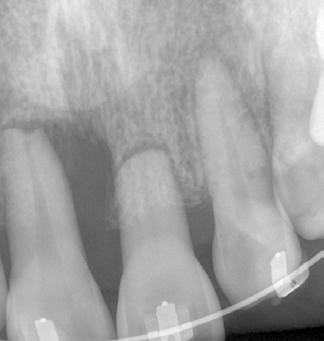

A 66-year-old male was referred for endodontic assessment of tooth 21. Tooth has been sensitive to cold and hot drinks and tender to biting. Extra and intra oral exam did not reveal any hard/soft tissue abnormality. The periodontal probing depth was within normal limits with bleeding on probing on palatal marginal gingiva of tooth 21 with no mobility. There was generalized attritive tooth surface loss due to parafunctional habit, although patient has been wearing an upper occlusal splint. The clinical investigations showed that the 21 was not tender to percussion and palpation. The 21 did not respond to cold and EPT pulp sensibility tests, in contrast to teeth 12, 11, 22 which responded to electric pulp tester. In order to assess the resorption and also peri-apical area, Two peri-apical x-rays taken from different angles. based on the radiographic assessment, tooth 21 found to have 1 root and 1 root canal. There was radiographic sign of invasive external resorption, with no peri-apical radiolucency.

The tooth 21 was diagnosed with acute exacerbation of a chronic irreversible pulpitis with clinically normal Peri-apical tissues and external invasive resorption grade 3 (without ankylosis but with communication to palatal surface in the mesial and distal aspects).

Treatment options discussed with patient in detail and the treatment plan was formulated as below:

Tooth investigation and endodontic treatment (if 21 was found suitable for further treatment) before followed by full coverage permanent restoration and preferably a new occlusal splint to protect tooth from crack or fracture.

Tooth investigation was performed under rubber dam isolation and root canal was

instrumented using EDTAC irrigation. There was excessive haemorrhage from the resorptive defect during the procedure, therefore a haemostatic agent used to achieve haemostasis. The tooth was found suitable for further treatment.

Ledermix (aspen®, Australia) was placed as the initial intra-canal medicament for 6 weeks. In the next session, root canal was medicated again with Ledermix for another 6 weeks. Calcium hydroxide paste (PULPDENT®, USA) was used thereafter as the final long-term intra-canal medicament for 12 weeks.

When patient presented after 3 months, he reported that the tooth was asymptomatic; therefore, it was decided to obturate the root canal system and seal the resorptive defect. ProRoot MTA (Dentsply Tulsa, OK, USA) paste was applied carefully under high magnification (ProErgo Microscope, ZEISS, Germany) to seal the resorptive defect. The apical half of the root canal system was obturated with gutta percha cones and AH 26 sealer (Dentsply DeTrey®, Germany) using lateral condensation technique. The mid coronal part of root canal and the resorptive defect was obturated with gutta percha pellets using warm vertical obturation technique. (Kerr Elements™ IC , Kerr Endodontics, USA).

Tooth was restored with glass ionomer cement (Fuji VII, GC Corp, Japan) and occlusion wad adjusted to remove any premature contacts in MI and eccentric movements.

After 6 weeks, patient reported tooth has been completely asymptomatic. A new PA x-ray showed satisfactory and well condensed root filling with normal peri-apical area. Patient was referred to general dentist for permanent restoration.

Radiograph 2

Radiograph 5

Radiographs

1. Pre-operative (19/10/2023)

2. Pre-operative radiograph with different angulation

3. Root canal instrumentation (9/11/2023)

4. Redressing of ledermix paste

Radiograph 3

2: Haemorrhage from resorptive defect after access cavity preparation

Radiograph 1

Radiograph 6

5. Pulpdent dressing

6. Root canal obturation and sealing the resorptive defect with MTA

7. After completion of root filling

Radiograph 4

Radiograph 7

Fig 1: pre-op photo of tooth 21

Fig 3: resorptive defect visible on palatal side